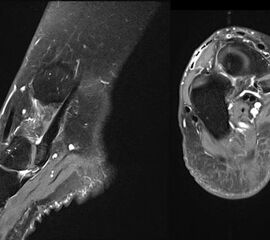

- Bei unklarem Befund kann die Bildgebung mittels MRTvervollständigt werden. Das MRT zeigt eine mögliche Aktivierung der Synchondrose bzw. erlaubt auch andere Differentialdiagnosen (Tendonose der Tibialis posterior Sehne, Verletzung Deltaband, Verletzung Pfannenband) auszuschließen (Abb. 3) 6 (Szeimies 2014).

Bei lange anhaltenden postoperativen Beschwerden ist die Rückfußstellung erneut zu überprüfen 22. Ein Rückfußvalgus führt zur einer Mehrbelastung des Ansatzes der Tibialis posterior Sehne, so dass ggf. die Indikation einer Kalkaneusosteotomie zur Korrektur der Rückfußachse zu überprüfen ist. Weitere mögliche Ursachen anhaltender Beschwerden kann eine unvollständige Abtragung der Knochenkanten sein, Beschwerden im Bereich der Narbe sowie eine Irritation der Tibialis posterior-Sehne. Als weiterführender Diagnostik empfiehlt sich in dieser Situation die MRT-Untersuchung, gegebenenfalls in Verbindung mit einer Computertomografie, da kleine Verkalkungen und Knochenkanten im MRT häufig übersehen werden.